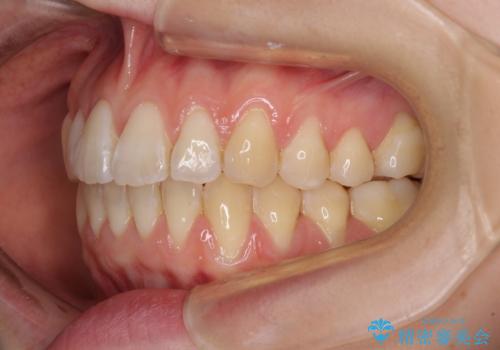

気になるデコボコとオープンバイト インビザラインでの矯正治療

- 前歯のデコボコと上下が開いていることを気にして来院された患者様です。

いわゆるオープンバイトは、インビザラインによる治療が適しているため、インビザラインにて治療を行うこととしました。

オープンバイトは容易に後戻りを起こすため、少しでも後戻りリスクを軽減するために舌癖改善のトレーニングをしっかりと行っていただきました。